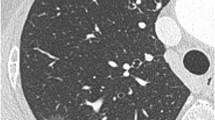

CT images of pGGOs. (a) A 38-year-old male with an AIS lesion in the posterior segment of the right upper lobe, appearing as a non-circular and blurred-margin pGGO with air bronchogram. (b) A 63-year-old female with an AIS lesion in the outer segment of the right middle lobe, appearing as a round and blurred-margin pGGO with spiculation and vascular convergence sign. (c) A 44-year-old male with an MIA lesion in the outer basal segment of the right lower lobe, appearing as a non-circular and clear-margin pGGO with spiculation, lobulation and vascular convergence sign. (d) A 28-year-old female with an MIA lesion in the posterior basal segment of the right lower lobe, appearing as a non-circular and clear-margin pGGO with pleural indentation. (e) A 43-year-old male with an MIA lesion in the outer segment of the right middle lobe, appearing as a round and blurred-margin pGGO with spiculation, vacuole sign and vascular convergence sign. AIS, adenocarcinoma in situ. MIA, minimally invasive adenocarcinoma. pGGO, pure ground-glass opacity.